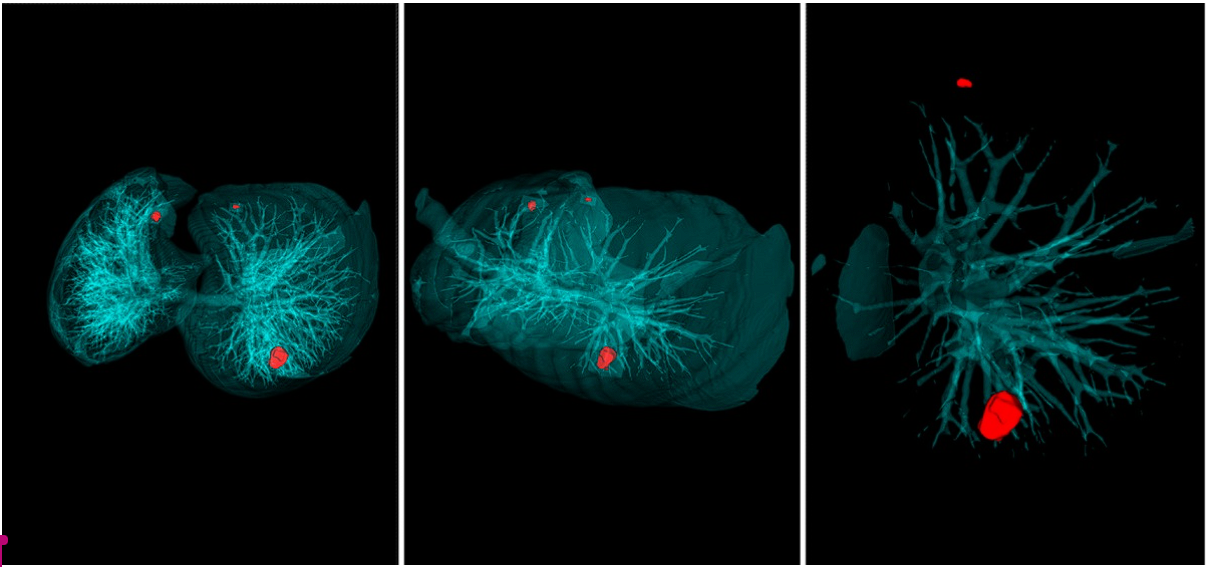

Метод хорд заключается в том, что на снимке компьютерной томографии на поверхность опухоли случайным образом помещаются точки, которые потом соединяются отрезками – хордами. Гистограмма длин этих отрезков отражает форму и структуру опухоли. Так ученые исследуют новообразование изнутри, но не менее важно, что окружает его снаружи. Для этого опухоль условно помещается в куб, а от его граней к поверхности новообразования проводятся перпендикуляры. Таким образом, вместо графически сложного и объемного снимка компьютерной томографии (его размер может достигать 1 Гб), опухоль представляется в виде компактных и простых гистограмм, которые и анализирует Doctor AIzimov.